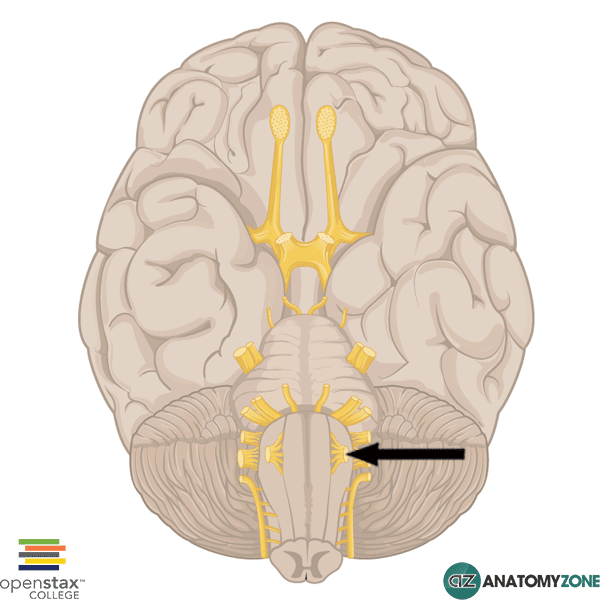

Hypoglossal Nerve – AnatomyZone

Hypoglossal Nerve (XII) and Canal